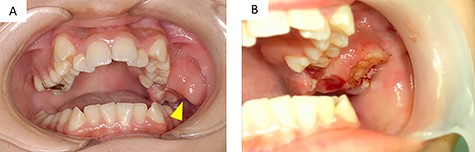

Panoramic radiography showed impaction of the left maxillary second molar and resorption of alveolar bone between the left maxillary molar area and the maxillary tuberosity (Fig. 2A).

Imaging findings; (A) a panoramic radiograph showing impaction of the maxillary second molar and resorption of alveolar bone between the left maxillary molar area and the maxillary tuberosity (arrowhead); (B and C) contrast-enhanced T-1 weighted MRI showing a high signal in the mass extending from the left masticator space to the buccal space and the maxillary and mandibular alveolar regions (arrowhead)

Computed tomography (CT) images showed a mass that extended from the left masticator space to the buccal space and the alveolar regions of the maxilla and mandible and pressure resorption of the anterior border of ramus, rear wall of the maxillary sinus and lateral plate of the pterygoid process. Involvement of the maxillary sinus was also suspected. Contrast-enhanced T1-weighted magnetic resonance imaging (MRI) showed a high signal in a range similar to CT (Fig. 2B and C). Contrast-enhanced effects in the left cervical and retropharyngeal (Rouviere) lymph nodes were also detected. 18F-fluorodeoxyglucose (18FDG)-positron emission tomography/CT showed a mass measuring 63 × 38 × 45 mm (long axis × minor axis × height) located in the left maxillary gingiva, accompanied by abnormal accumulation of 18FDG (standardized uptake value [SUV] max, 8.3), and left cervical lymphadenopathy, accompanied by abnormal accumulation of 18FDG (SUVmax, 41.72), which was suspected as metastasis. Abnormal accumulation was not observed in the other organs.